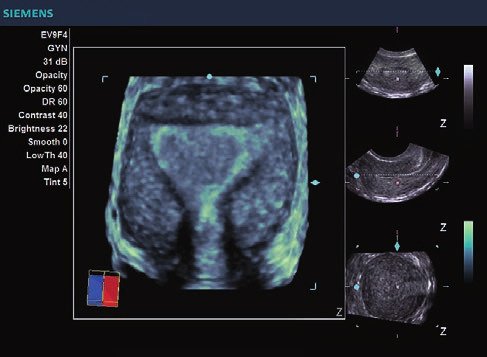

Siemens ACUSON X300 PE Beschreibung

• Features: 3D, 4D, Farb/Doppler

• Gynäkologie/ Geburtshilfe

• Gynäkologie